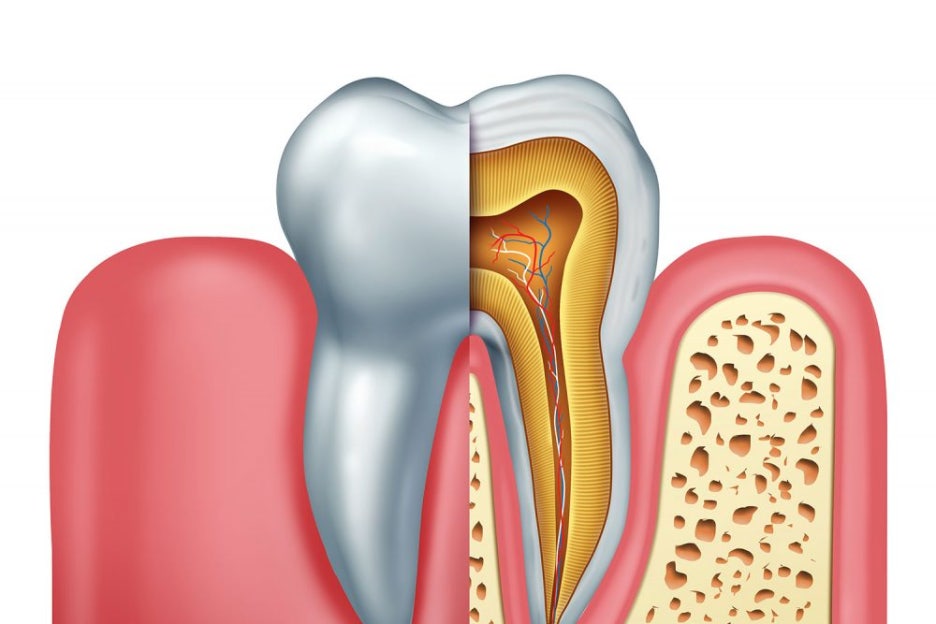

치아의 단면도를 살펴보면

그냥 잇몸 속에 묻혀 있는 것 같던 게

알고 보면 치조골이라는 뼈에 고정되어 있습니다.

더불어 주변에 있는 치주 인대와 같은 조직들의 도움을 받아

단단히 고정되어 제 역할을 하고 있는 것이죠.

『만약 이 뼈의 상태가 좋지 않으면 어떻게 될까요?』